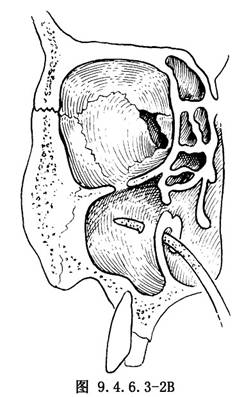

3.開窗 於下鼻道已暴露的骨壁處用上頜竇彎形骨銼穿刺至上頜竇(圖9.4.6.3-2)。